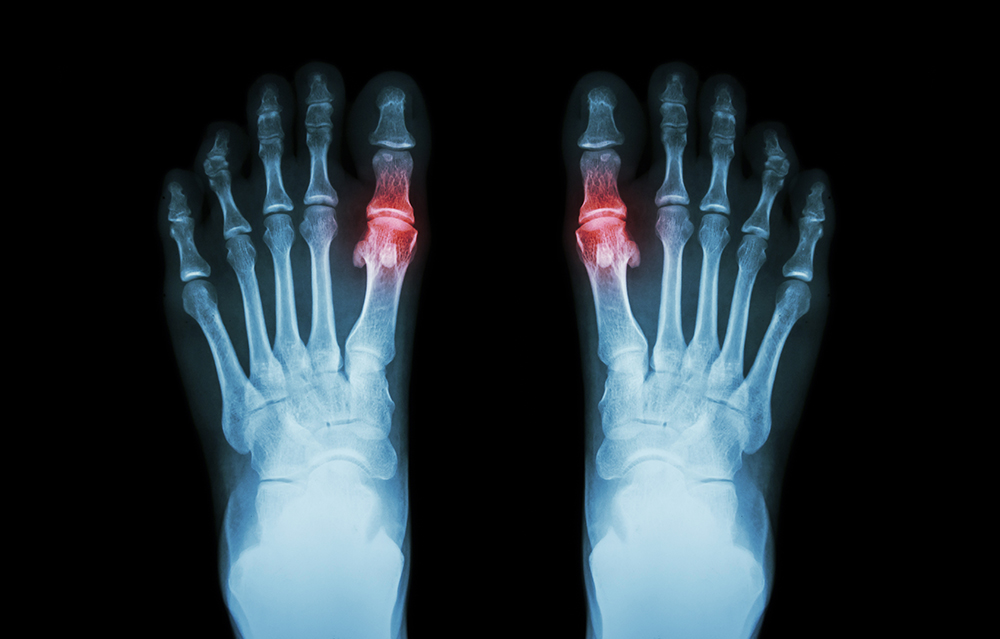

OPERACJA/PLASTYKA PALUCHA KOŚLAWEGO, SZPONIASTEGO, MŁOTOWATEGO.

Operacja plastyczna najczęstszej deformacji nabytej czyli palucha koślawego jest zabiegiem operacyjnym mającym na celu uwolnienie pacjenta od dolegliwości bólowych po przyśrodkowej stronie palucha (tzw: bunionu) oraz na podeszwie stopy wynikające z płaskostopia poprzecznego wystepujące zwykle wtórnie do palucha koślawego przy współistniejącej poprawie efektu wizualnego samej stopy. Bardzo częstą deformacją współistniejącą do palucha koślawego są palce młotowate lub/i szponiaste, które także poddaje korekcji się podczas tego samego zabiegu operacyjnego dla uzyskania pełnego efektu terapeutycznego.